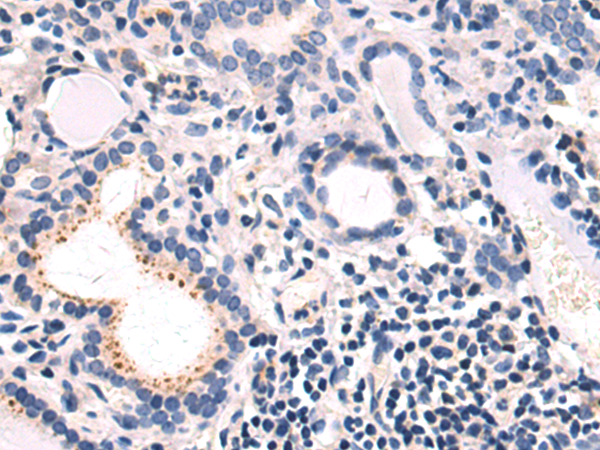

分类: 科研抗体货号: P13788别名: CAM2; CAMK2; CAMKB; MRD54; CaMKIIbeta应用: WB,IHC反应种属: Human

分类: 科研抗体货号: P13787别名: PKACB; PKA C-beta应用: WB,IHC反应种属: Human, Mouse, Rat

分类: 科研抗体货号: P13809别名: CLM; LIS5应用: WB,IHC反应种属: Human, Mouse

分类: 科研抗体货号: P13786别名: NUMA; NMP-22应用: IHC反应种属: Human, Mouse

分类: 科研抗体货号: P13806别名: NT3; HDNF; NGF2; NT-3; NGF-2应用: IHC反应种属: Human, Mouse, Rat

分类: 科研抗体货号: P13818别名: P15; MTS2; TP15; CDK4I; INK4B; p15INK4b应用: WB,IHC反应种属: Human

分类: 科研抗体货号: P13825别名: PP68; NSAP1; GRYRBP; HNRNPQ; HNRPQ1; GRY-RBP; hnRNP-Q应用: IHC反应种属: Human, Mouse, Rat

分类: 科研抗体货号: P13805别名: ACO; HSRNASPH应用: WB,IHC反应种属: Human, Mouse

分类: 科研抗体货号: P13817别名: DUBA8; OTUD2; PRO0907应用: IHC反应种属: Human, Mouse, Rat